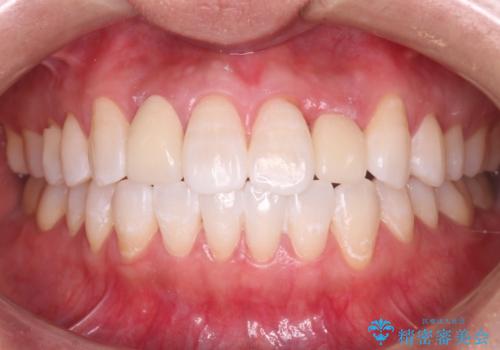

最新の症例

Latest cases